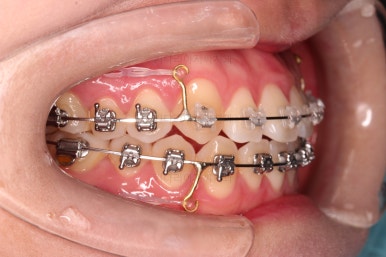

4. 치료 진행 상황

부산치아교정잘하는곳 키다리아저씨치과에서 사용한 장치는 엠파워라고 하는 자가결찰 장치인데요.

이번 환자분은 윗니는 세라믹, 아랫니는 메탈로 선택을 하셨습니다.

웃을 때 더 많이 보이는 부분은 좀 더 심미적인 세라믹으로 하고, 아랫니는 메탈도 상관없다고 하여 조합해서 사용했는데요.

동일한 회사의 동일한 규격의 장치라 혼용해서 써도 무방합니다.

장치 부착한지 얼마 안되어 치열은 매우 고르게 되었는데요.

치료 목표는 그것 뿐만 아니라 입을 조금이라도 넣고, 앞니 각도도 개선해야 되었으므로 사랑니는 모두 뽑아내고 미니스크류를 활용해서 뒤로 뒤로 밀어넣습니다.